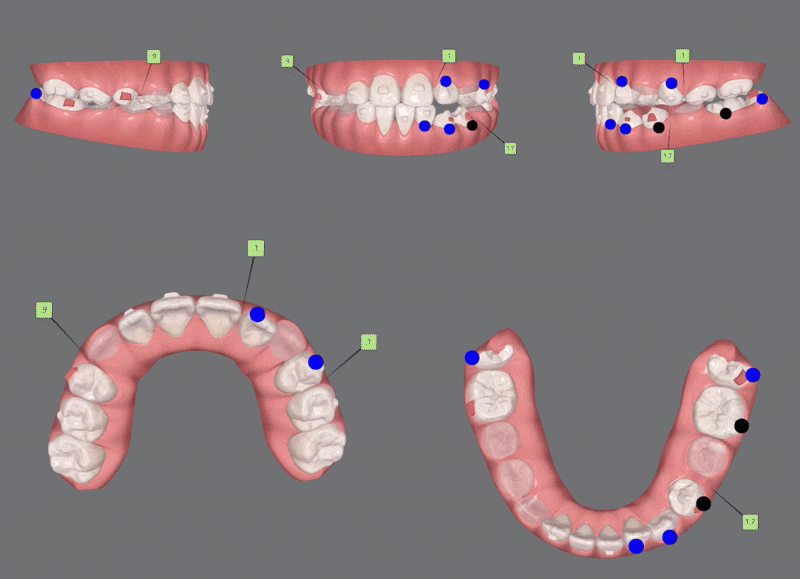

1st Clincheck(30개)

첫번째 클린체크에는 30개의 인비절라인장치로 진행해드렸습니다.

클린체크대로

악궁이 확장되며 점차 정상적인 교합으로 변화되었습니다.